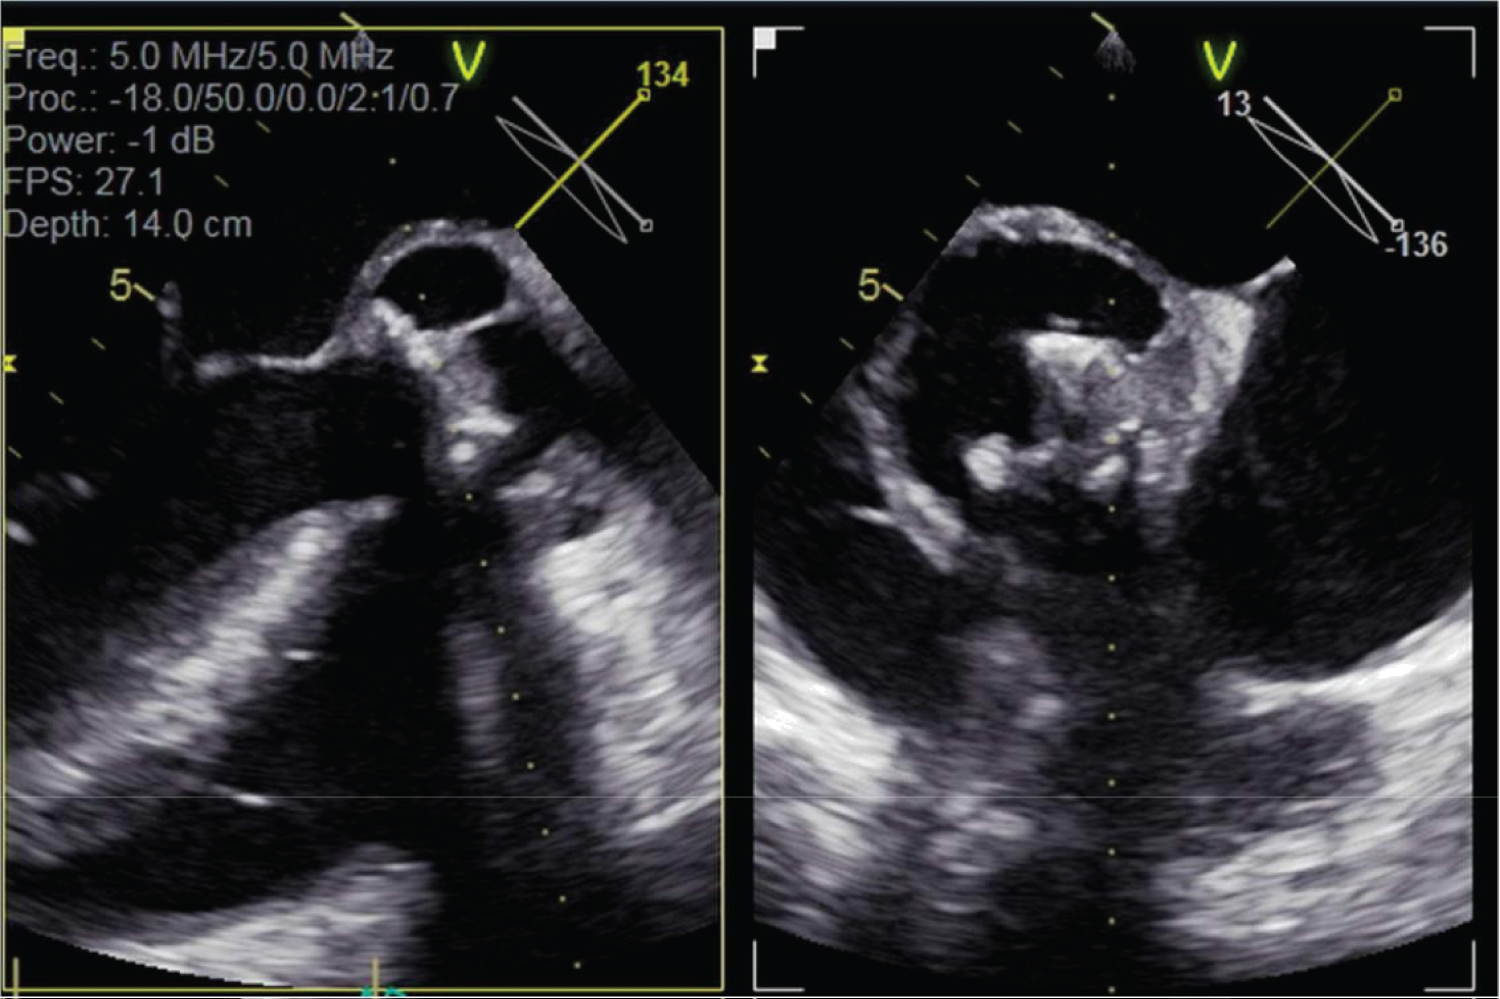

Figure 3: Transoesophageal echocardiogram multiplane images through aortic valve and aortic root.

Large echodense space around Mosaic heterograft consistent with aortic root abscess, in addition to multiple gross echo densities on bioprosthetic valve leaflets. View Figure 3

Transoesophageal echocardiogram was promptly performed which confirmed the findings on transthoracic echocardiogram. A large echodense space around the heterograft was identified, consistent with abscess and fistula into the left ventricular outflow tract, in addition to a large echodensity of the bioprosthetic valve leaflets, and valve annular rocking (Figure 3 and Figure 4).